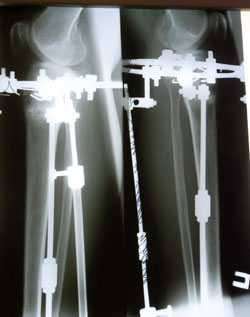

Дата операции 10.06.2014г.

Дата снятия 30.09.2014г.

Срок лечения 110 дней.